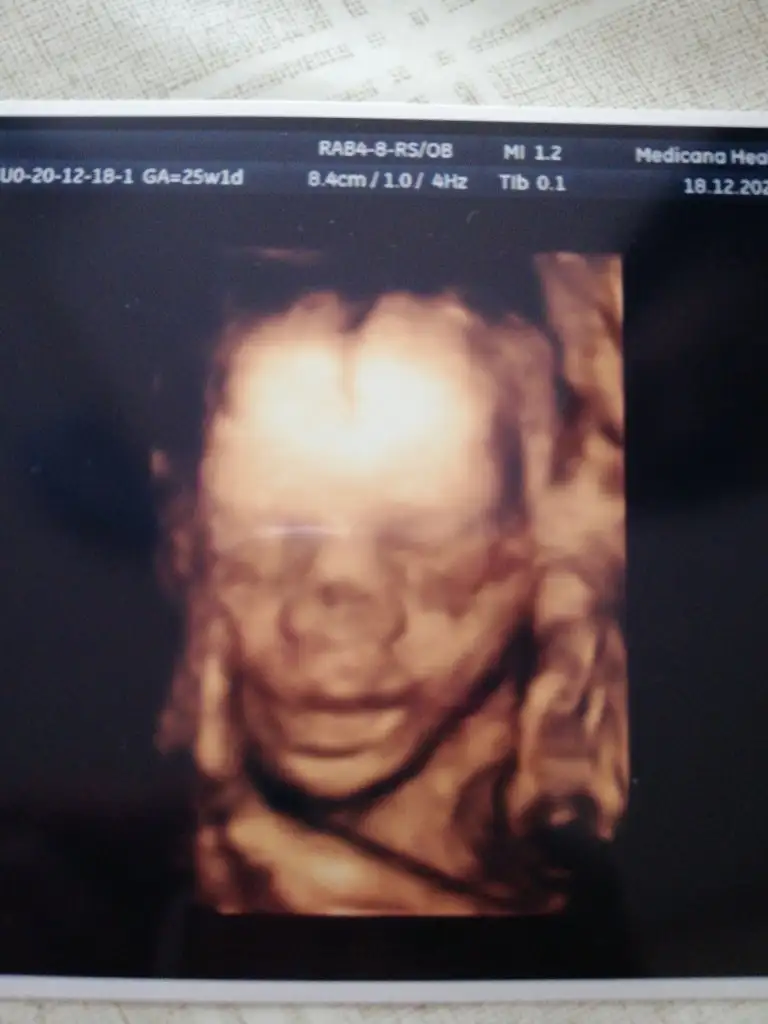

Canım instegramda aradım bu hesabı bulamadım![]()

Açlık 87 çıktı 50 lik yüklemeden sonra 101 çıktı şekerim.Valla büyüyorlar canım ya..Pozisyon ile ilgili birşey demedi doktor inan ben de yüzünü görünce neresi nerde hiç bakmadım..Renkli fotomuz da böyle insana benzedi iyiceayyy cok sevindim seker testini gectinmi sonuclar ciktimi? insallah yoktur seker. bak sen cimcimeye koca kiz olmus masallahay artik kilolarida hizla artiyor doguma dogru gidiyoruz